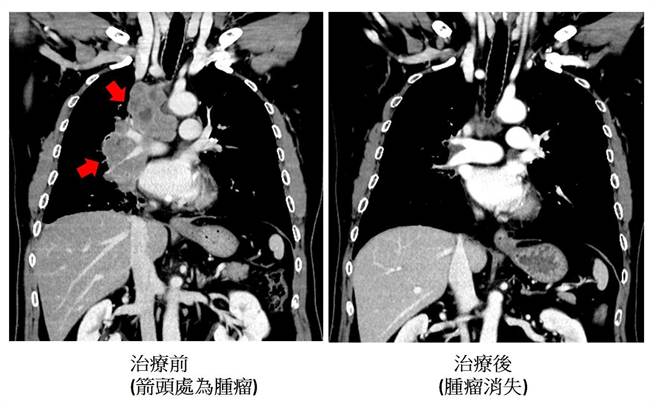

40年老菸枪接受化学治疗同时合併免疫治疗,他在化学治疗疗程结束后亦继续接受免疫治疗,现已持续超过一年半,后续追踪发现肺肿瘤几乎全消失。(澄清医院提供/冯惠宜台中传真)

刘旭崇说,该患者配合接受此合併治疗,一两个疗程后,其临床症状与影像学检查均改善很多,他在化学治疗疗程结束后亦继续接受免疫治疗,现已持续超过一年半,后续追踪发现肺肿瘤几乎全消失,连转移脑部与骨头的肿瘤也消失,达到临床上完全缓解的状态。他目前活得很有信心且症状改善很多,颠覆了「小细胞肺癌」患者活不久的传统印象。刘旭崇指出,免疫治疗合併化疗为小细胞肺癌患者提供新的选择与希望。